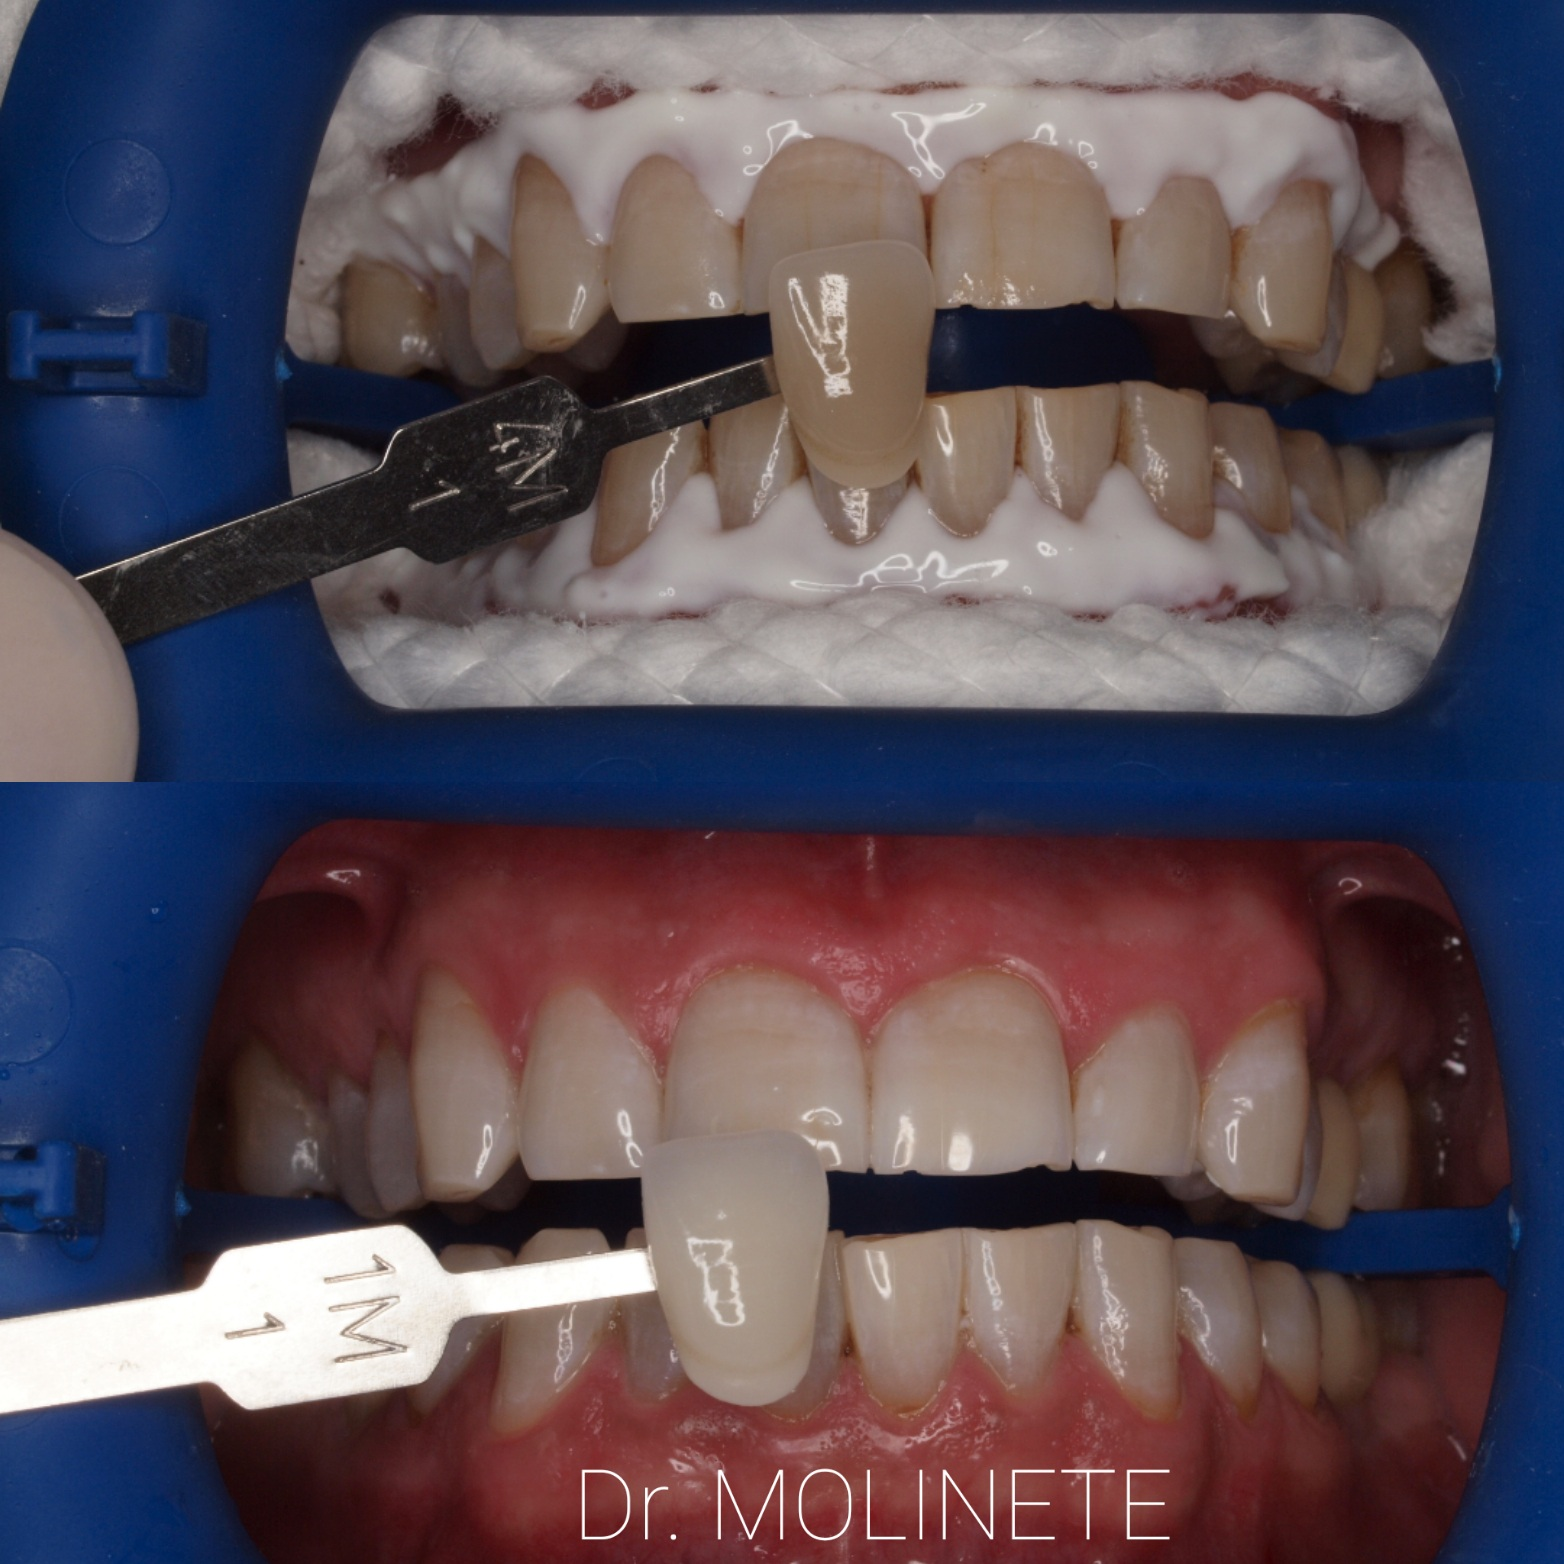

Blanqueamiento dental